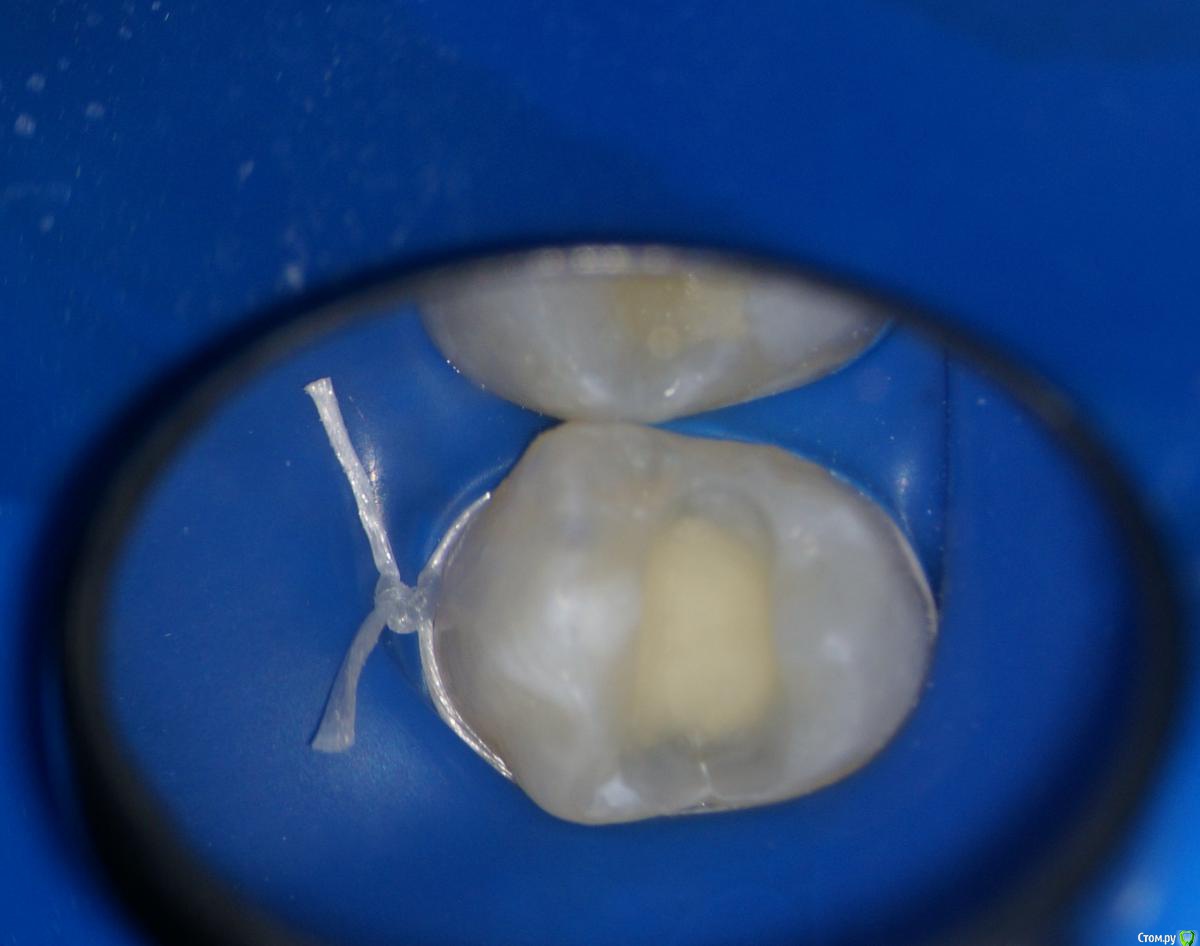

Л Ю С Я Опубликовано 10 января, 2014 Поделиться Опубликовано 10 января, 2014 .Новый кейс-совсем свежий пока без долгосрочного результата.Пациентка попала случайно удаляла зуб 28 и хирург сделал ОПТГ,где стали видны обширные периапикальные процессы в области 37 47.Побывав у меня на консультации и услышав план лечения и стоимость,пациентка решила видимо полечить подешевле.,побывав на консультациях в нескольких клиниках и в итоге даже попала к главному стоматологу нашей области. Все ей сказали что удаление онли. Вернулась,-засада была в том что план я писал исходя из ОТПГ не сделав прицел(виноват),сделав прицел понимаю что все сложнее чем я думал-ну что же тем интереснее.Переписав план лечения и подняв ценник на 40%(пациентке не оставалась выбора),начали лечение.1-посещение-ревизия пломбы.понимаю что кто то до меня с маниакальным упорством пытался запломбировать мезиальный язычный канал каналонаполнителями. Убрал два фрагмента из верхней трети мезиального язычного.2-посещение еще фрагмент из мез язычного плюс немного с дистальными поработал(их оказалось два сплит в верхней трети)3-визит обошел фрагмент в мезиальном щечном и доработал остальные каналы.4-визит -паковка.На предпоследнем снимке видны поры-допаковал(просто на финальном не очень видно)Класс! Ждем рекол через 6 месяцев. Паковка чем? Сквирт? Ссылка на комментарий

Hans85 Опубликовано 10 января, 2014 Автор Поделиться Опубликовано 10 января, 2014 Не чистый сквирт-скорее гибрид не знаю как правильно назвать -в общем сначала сквирт а затем дополнительно разогрев плаггером и уплотнение.Просто аппарат для сквирта пока не айс(Бифилл) ну вот клинику откроем там будет по фен-шую - ГуттаИзи. Ссылка на комментарий